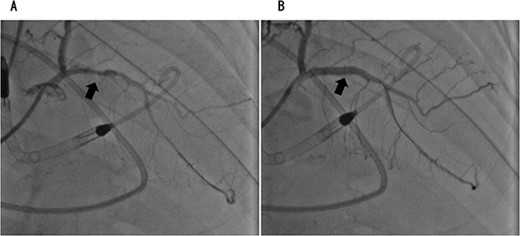

Coronary angiography showed 100% occlusion of the left circumflex branch (A). After the procedure, the occlusion was completely released (B).